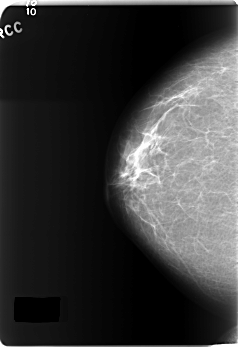

C_0163_1.RIGHT_CC

C_0163_1.LEFT_CC

LEFT_CC LINES 6000 PIXELS_PER_LINE 3360 BITS_PER_PIXEL 12 RESOLUTION 50 NON_OVERLAY

RIGHT_CC LINES 5896 PIXELS_PER_LINE 4032 BITS_PER_PIXEL 12 RESOLUTION 50 NON_OVERLAY